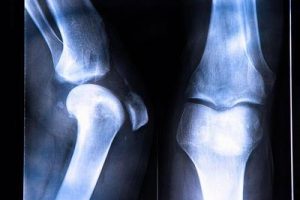

交叉韧带是膝关节内对于保持关节稳定至关重要的两根韧带,根据其位置分为前交叉韧带和后交叉韧带。前交叉韧带是膝关节内重要的韧带之一,起着限制胫骨前移、膝关节过伸及小腿内外旋及外展内收等作用,也是膝关节内最容易受伤的韧带。 什么是前交叉韧带损伤?...

由于运动伤、交通伤的增多,前交叉韧带损伤呈上升趋势,一般来说,损伤可分为Ⅰ~Ⅲ级,不同的损伤程度处理起来也是不一样的,损伤后我们要及时判断损伤的程度,然后做出针对性的处理。具体损伤程度需要通过专业医生来判断,我们自己无法确定自己具体的损伤程...

前十字韧带起源于股骨远端外侧髁的内面。发生前十字韧带断裂的主要原因是运动损伤,15~25岁的专业运动员为多发群体,尤其是包含大量身体转动的运动,如篮球、足球及滑雪运动等。女性发生率高于男性。前十字韧带扭伤时,内侧副韧带及内侧半月板可能随之发...

当出现前交叉韧带撕裂,患者会出现行走困难的情况,日常生活也会受到影响。而前交叉韧带撕裂多发生于运动损伤,运动员中也有很多出现前交叉韧带撕裂的情况,患者通常会选择前交叉韧带重建手术,帮助治愈韧带,但是手术带来的后遗症也是患者需要了解的。 1....